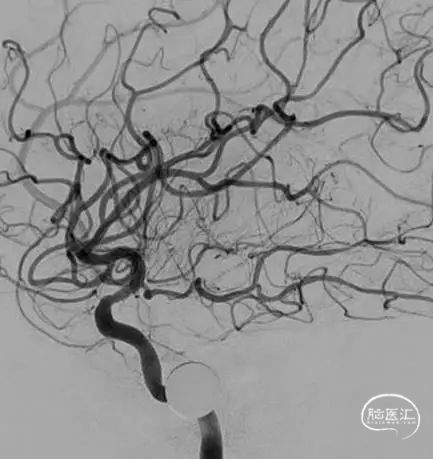

前交通开放代偿右侧大脑中动脉。

后循环未向右侧大脑中动脉代偿供血。

病变展示:右侧颈内动脉后交通段次全闭塞。